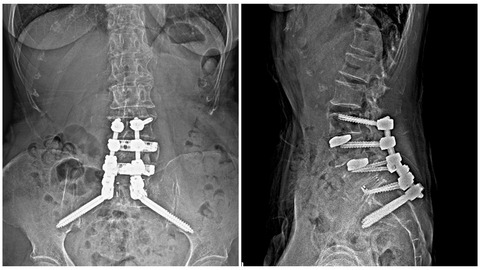

SAIスクリューを刺入してロッド連結も一直線にいきました!

②あと、ロッドが連結しやすいよう、SAIのヘッドと腰椎スクリュー、S1スクリューのヘッドの位置を一直線になるようにプランニングします。

テクノロジーの進歩は凄まじいものがありますね。

SAIとPES、CBTは相性がとてもいいように思われます。

これまで何度もtear dropを確認しながらフリーハンドで打っていたSAIですが、これからはテンプレートで方向が正しいことが確認されれば、何度も何度も透視で確認することが要らなくなりますね。

いやあ、それにしても俊逸でした。

この技術のおかげでSAIをより確実に刺入できるようになったと思いました!